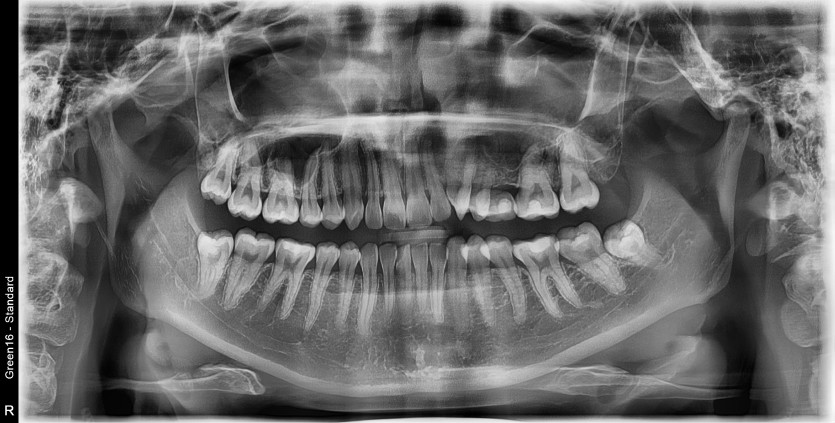

#18,48 사랑니 발치

구강외과 전문의가 당일 발치 했씁니다.